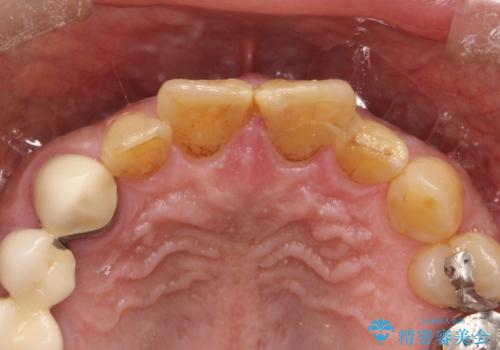

左上1が水平的に割れている状態で、歯冠を取り除くと神経が露出しており、唇側はかなり歯肉縁下で破折しており、そのままではかぶせものを入れるのは難しい状態でした。

根管治療をした上で歯を引っ張りだして(エクストリュージョン)、その後、骨外科にて歯周組織を整えた上で、かぶせものを入れていく治療計画をたてました。